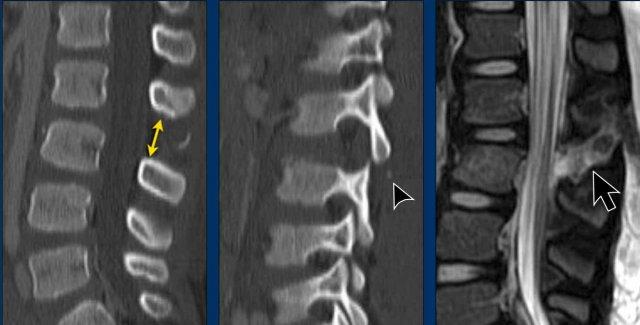

These images are of a young child with a spinal injury.

Findings

- Clear widening of the interspinous distance (yellow arrow)

- Black arrowhead: small avulsion fracture to the flexion distraction

- MRI better depicts the ligamentous injury, which was suspected on CT

Conclusion

Injury type B2

- Subtle widening of the interspinous distance (white circle)

- Small avulsion fracture spinous process (yellow arrow)

- Compression fracture with involvement of one endplate and posterior wall (1+2 points)

Injury type B2 + A3